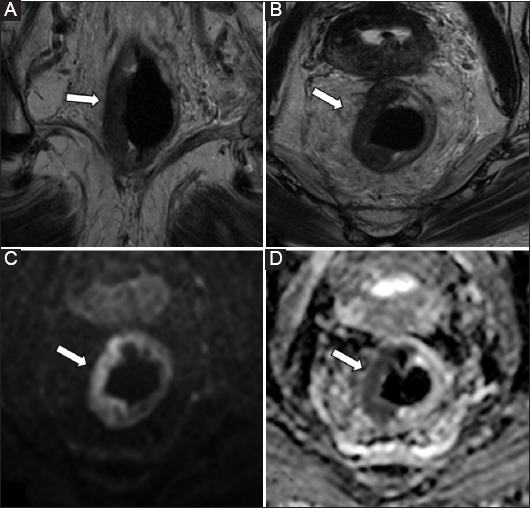

Based on our experience, in 14% of patients, T2-weighted imaging was not successful in differentiating perirectal inflammation from tumor invasion, resulting in overstaging (Fig. 2). Notably, our failure rate is consistent with the level of overstaging reported in a previous study on T3 tumors, which ranged from 11-16% [6]. Several studies have emphasized this limitation, highlighting the technical inability of T2-weighted imaging alone to reliably discriminate a desmoplastic reaction from tumor infiltration into the mesorectal fat [13,21,32,37-40]. In our series, all overstaged cases exhibited linear or band-like signal abnormalities within the mesorectal fat, which were interpreted by both readers as early signs of extramural tumor invasion. However, it is well established that MRI cannot effectively distinguish desmoplastic reactions from true extramural tumor infiltration, particularly in the absence of a nodular morphology [38]. In contrast, DWI had promising results in the characterization of peritumoral tissues, compared with conventional MRI, taking advantage of tumor hypercellularity. In the current study, DWI exhibited a high diagnostic performance across all tumor stages, achieving superior sensitivity and specificity (91.43-100%) compared with conventional MRI. These findings are consistent with those of previous studies [30,32,37]. However, they provide a novel perspective. In particular, the adjunctive use of DWI had remarkable accuracy in early-stage (T1-T2) tumors, which are traditionally considered challenging to stage using MRI [13]. Based on our experience, the addition of DWI significantly improved the sensitivity of conventional MRI, particularly for assessing T2 and T3 tumors, which are critical stages in determining the most appropriate treatment strategy (Fig. 3). This improvement may contribute to a reduction in overstaging, thereby sparing more patients from unnecessary presurgical chemotherapy. In our cohort, DWI (97.01%) had a higher sensitivity for T3 tumor staging than conventional T2-weighted sequences (91.43%), indicating an excellent positive predictive value. To the best of our knowledge, previous studies have not assessed the potential of DWI for predicting T3 stage with such high accuracy, nor have they included such a large patient cohort. Notably, only 1 recent study, which included a cohort of 81 patients, showed that DWI had a good predictive value in evaluating the depth of muscularis propria invasion in mid- to high-rectal cancers, emphasizing its potential utility in preoperative staging [41]. However, the study used a purely quantitative DWI approach, relying on the manual assessment of ADC map values, which may limit its generalizability in clinical practice. In our opinion, this technique is labor-intensive, prone to interscanner variability, and strongly influenced by distortion inherent to DWI that may influence the precision of ROI boundary assessment. By contrast, our study used a more practical and reproducible approach, which is in accordance with routine clinical practice, based on the qualitative assessment of DWI signal characteristics and T2-weighted imaging, without the need for segmentation or quantitative mapping.

thumblarge

Figure 3 A 52-year-old patient with low-rectal cancer. High-resolution coronal (A) and axial (B) T2-weighted images showing a rectal neoplasm involving the left lateral wall of the rectum, with a focal inhomogeneous area at the 10 o’clock position (arrow), raising suspicion for extramural invasion. Axial diffusion-weighted image (C) and corresponding apparent diffusion coefficient (ADC) map (D) revealing a small extramural component (arrows) with diffusion restriction and significantly low ADC values. Histopathological analysis confirmed mesorectal infiltration (stage T3b)